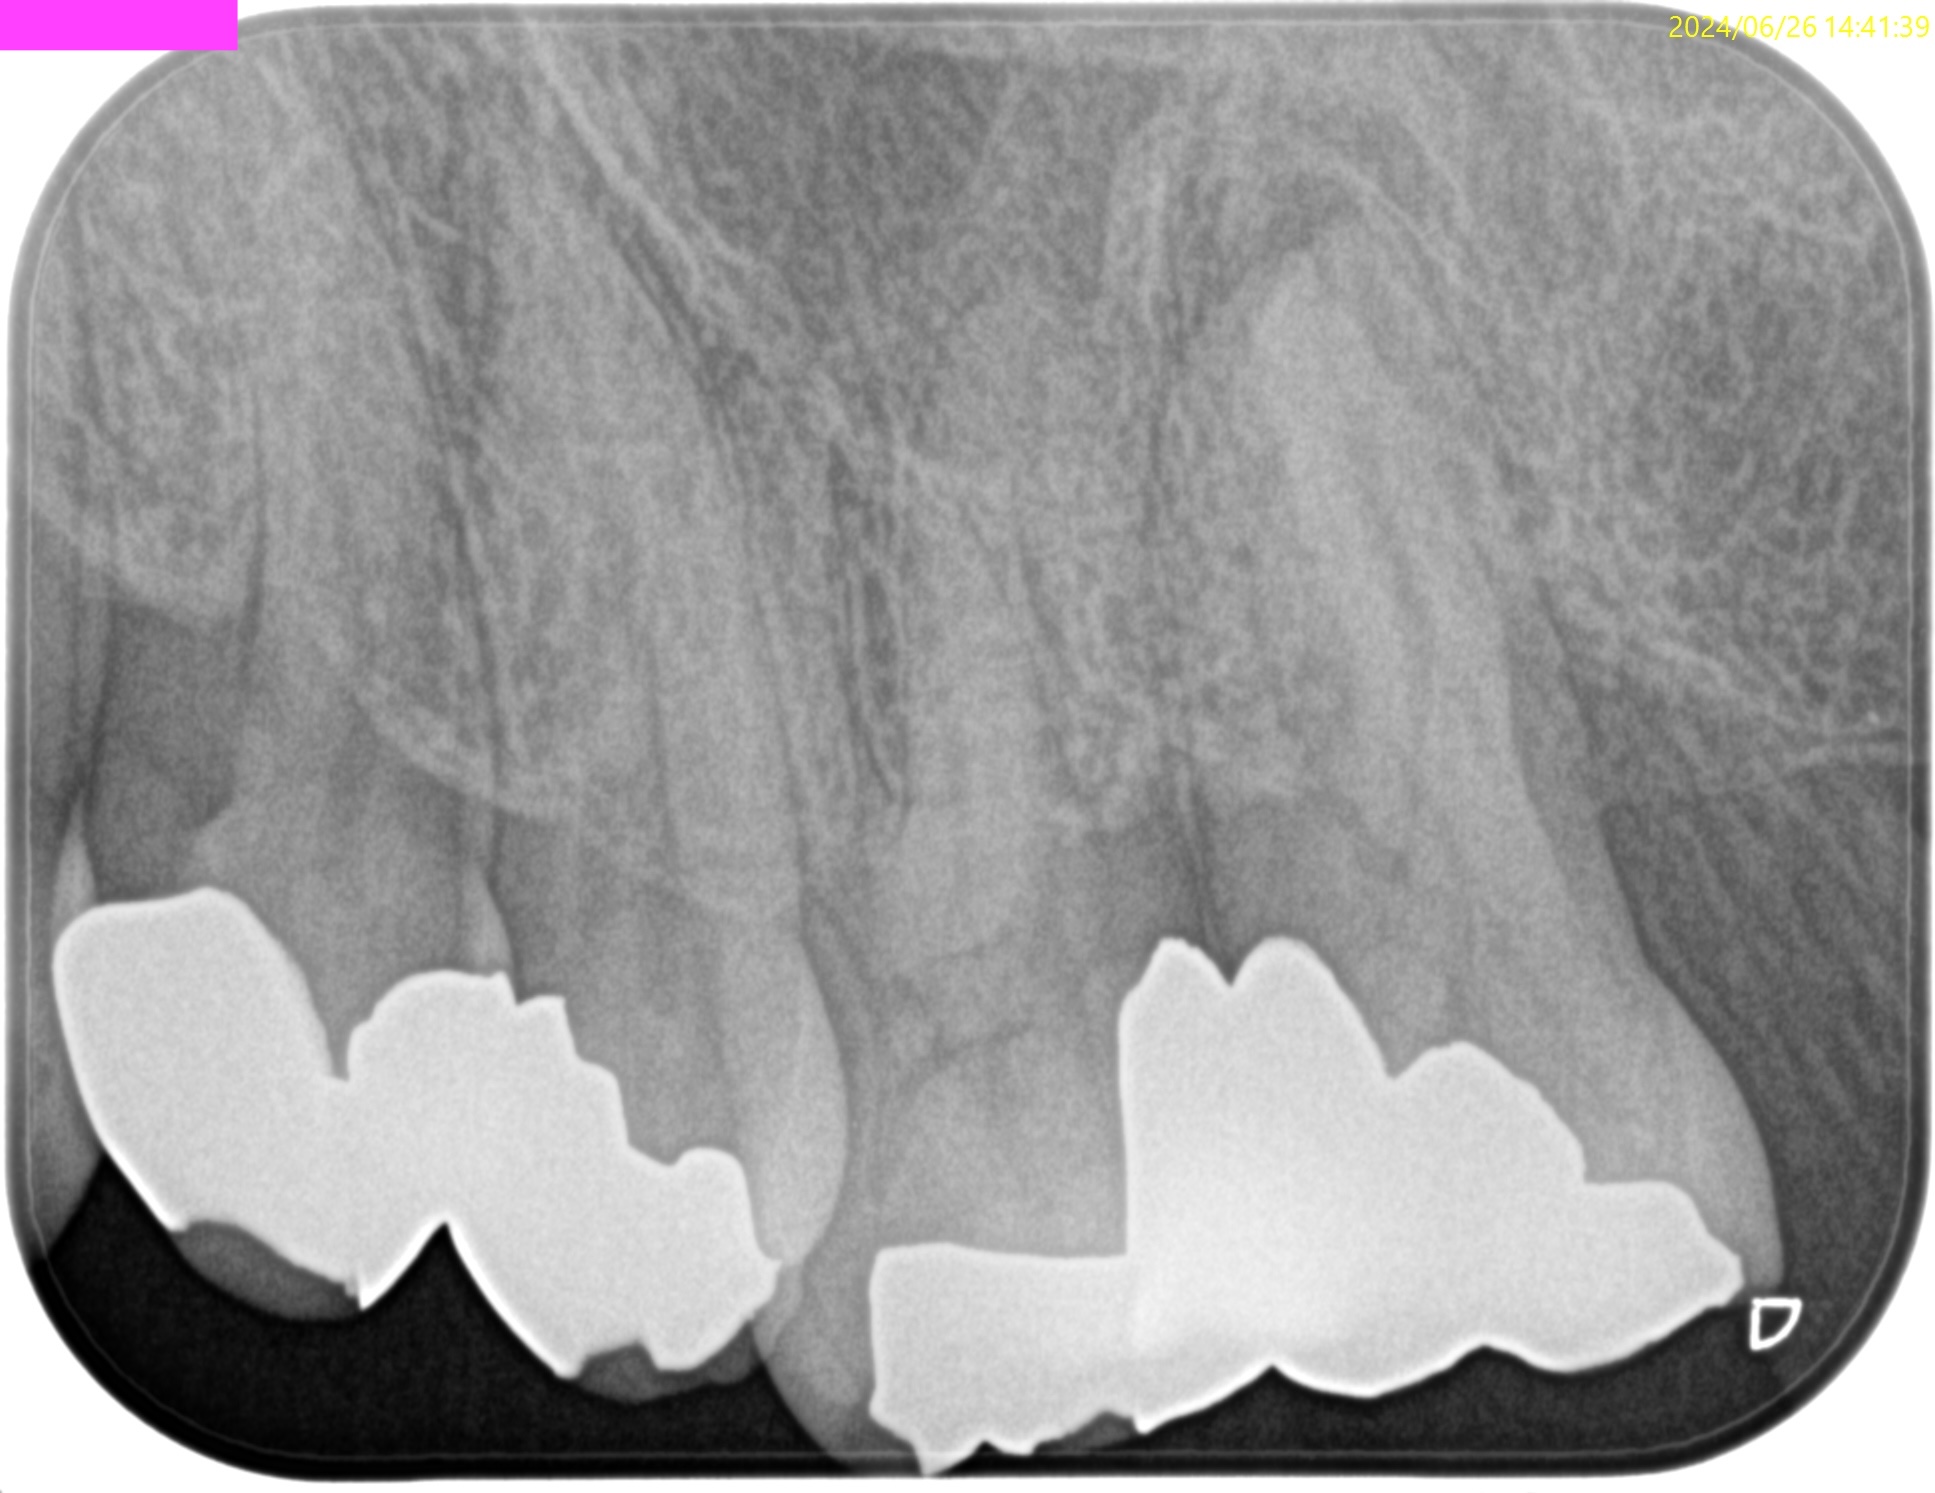

Pre-op Endo Test(2024.7.31)

PA(2024.7.31)